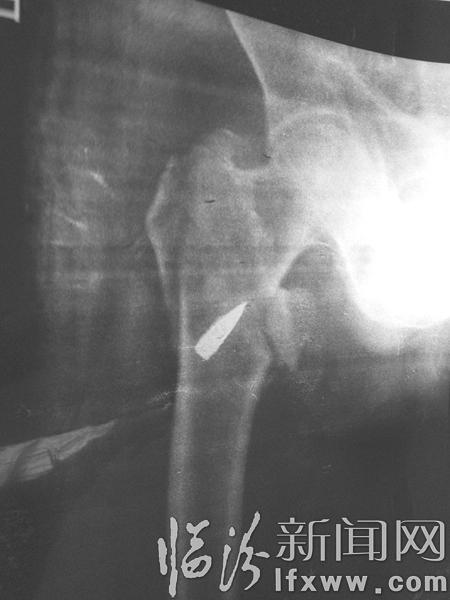

2005年,那年孙德成老人72岁。有一天,他蹲下再站起来时,突然觉得右腿股骨头处像针扎一样疼,虽然就是当年受伤的位置,可他只当是肌肉疼,根本没有想别的,咬咬牙继续往前走,没走多远,他竟然一个踉跄,身不由己地摔倒在地。在医院的X光下,大夫吃惊地发现,他的股骨头里竟然嵌着一粒子弹!

这粒子弹的外面被一层铜壳包着,幸亏铜的性质在骨头中比较稳定,虽然多年过去了,可它还是完整地包裹着里面的铅芯,否则,铅芯会不断释放铅元素,导致人体铅中毒。

孙德成这才想起,自己当年在朝鲜战场天天处身弹片横飞的环境中,中弹受伤也在所难免。那是1952年7月的一天,运输途中,孙德成遭遇飞机往下扫射,他的右腿三处受伤,被送到团部卫生所,当天晚上,医生在马灯下为他做了手术,从右腿膝盖下取出了两粒子弹,并给他臀部的一处伤口作了包扎。在当时来看,他这样的伤根本算不上什么,养伤一个多月后,他归队了。由于条件所限,根本不能做进一步的检查,由于当时臀部伤处并不是很疼,谁也不会想到,竟然会有一粒子弹遗留在他的股骨头里,从此与他相伴半个多世纪!

虽然查出了问题的根源,可是,经过综合分析,家人还是放弃了将这粒子弹取出来的打算:年纪大了,活动不方便就不方便吧,只怕手术时一全麻醒不过来。”就这样,这粒子弹继续在孙德成的身体里又待了11年,至今还在,并将一直伴随他。

当年,在朝鲜战场上孙德成曾经荣立二等功,然而,由于当时情况特殊,他的这份殊荣只是记载在《复员证》上,子弹,这份特殊的“军功章”却一直记载在他的身体里!